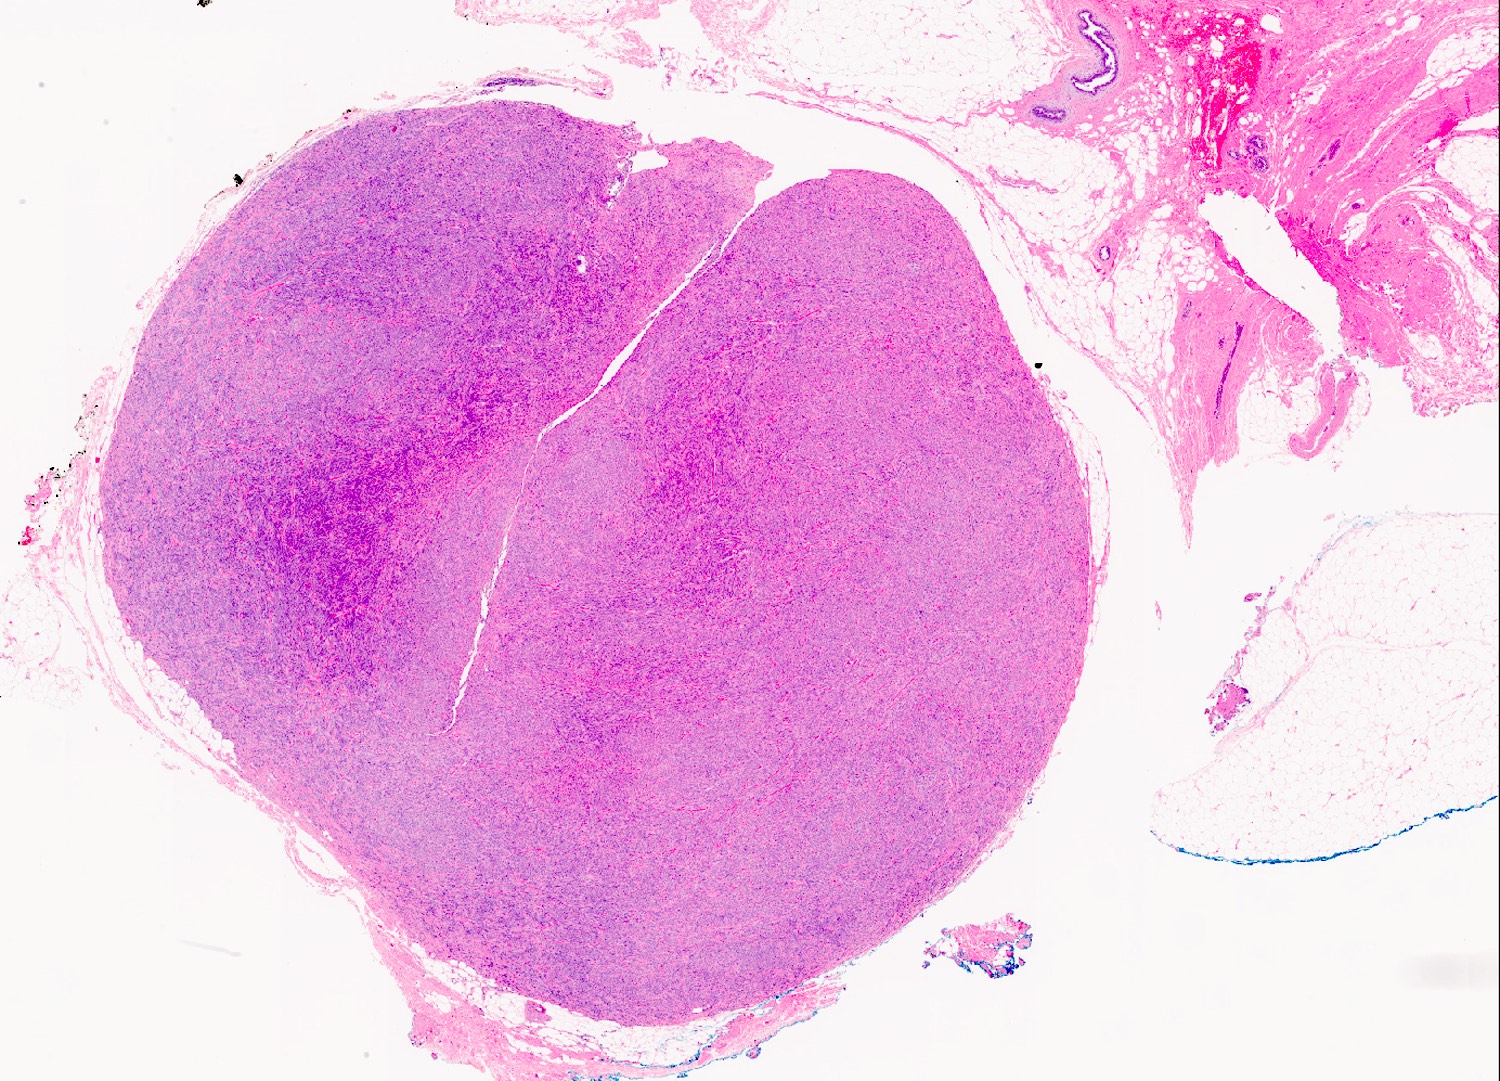

Microscopic (histologic) images

- Well circumscribed, lacks true capsule, rarely infiltrative

- Bland, uniform, short to elongated spindle cells arranged as short haphazard intersecting fascicles admixed with bands of hyalinized, brightly eosinophilic collagen and variable amounts of fat

- No more than mild nuclear atypia

- Mitoses usually absent, atypical mitoses and necrosis absent

- Mast cells common, perivascular lymphocytic infiltrates on occasion

- Focal myxoid stromal changes common